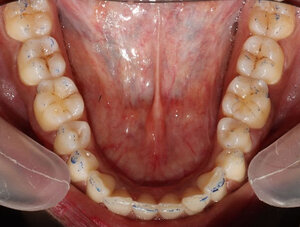

Thirty-one TN patients diagnosed at a Neurology Clinic (The National Institute of Mental Health & Neurosciences, Bengaluru, Kamataka, India), were referred to a prosthodontic dental office with chief complaints of Trigeminal Neuralgia pain to undergo a digital occlusion and muscle physiology evaluation. In addition to TN problems, some of the referred patients demonstrated chewing fatigue, chewing pain, chewing weakness, ongoing head, neck and facial pain and ongoing tension, and headaches around the eyes, midface and temples. All of these patients had anterior teeth that coupled or nearly coupled, demonstrated relatively normal occlusal relations. (Figures 1a, 1b & 1c), and presented with minimal or no Temporomandibular Joint structural breakdown.